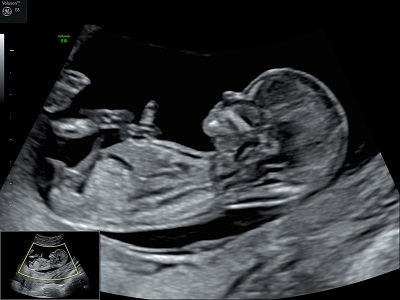

"Voir ce qui est invisible, grâce à des sons inaudibles."

En tant que profession médicale, nous pouvons pratiquer toutes les échographies de dépistage au cours de la grossesse, ainsi que les échographies pelviennes (gynécologiques), après l'obtention d'un diplôme inter-universitaire d'échographie obstétricale et gynécologique.

Nous sommes agréées pour la mesure de la clarté nucale dans le cadre du dépistage de la Trisomie 21.

Nous utilisons pour réaliser nos examens un échographe performant, le Voluson E8 de chez General Electric. Ainsi, il n'est plus nécessaire de boire beaucoup d'eau avant une échographie.

En revanche, il est recommandé de ne pas appliquer de corps gras (crèmes ou huiles) sur votre ventre 5 jours avant votre rendez-vous afin que l'image soit la plus nette possible.

Nous réalisons les 3 échographies obstétricales recommandées pour le suivi de la grossesse.